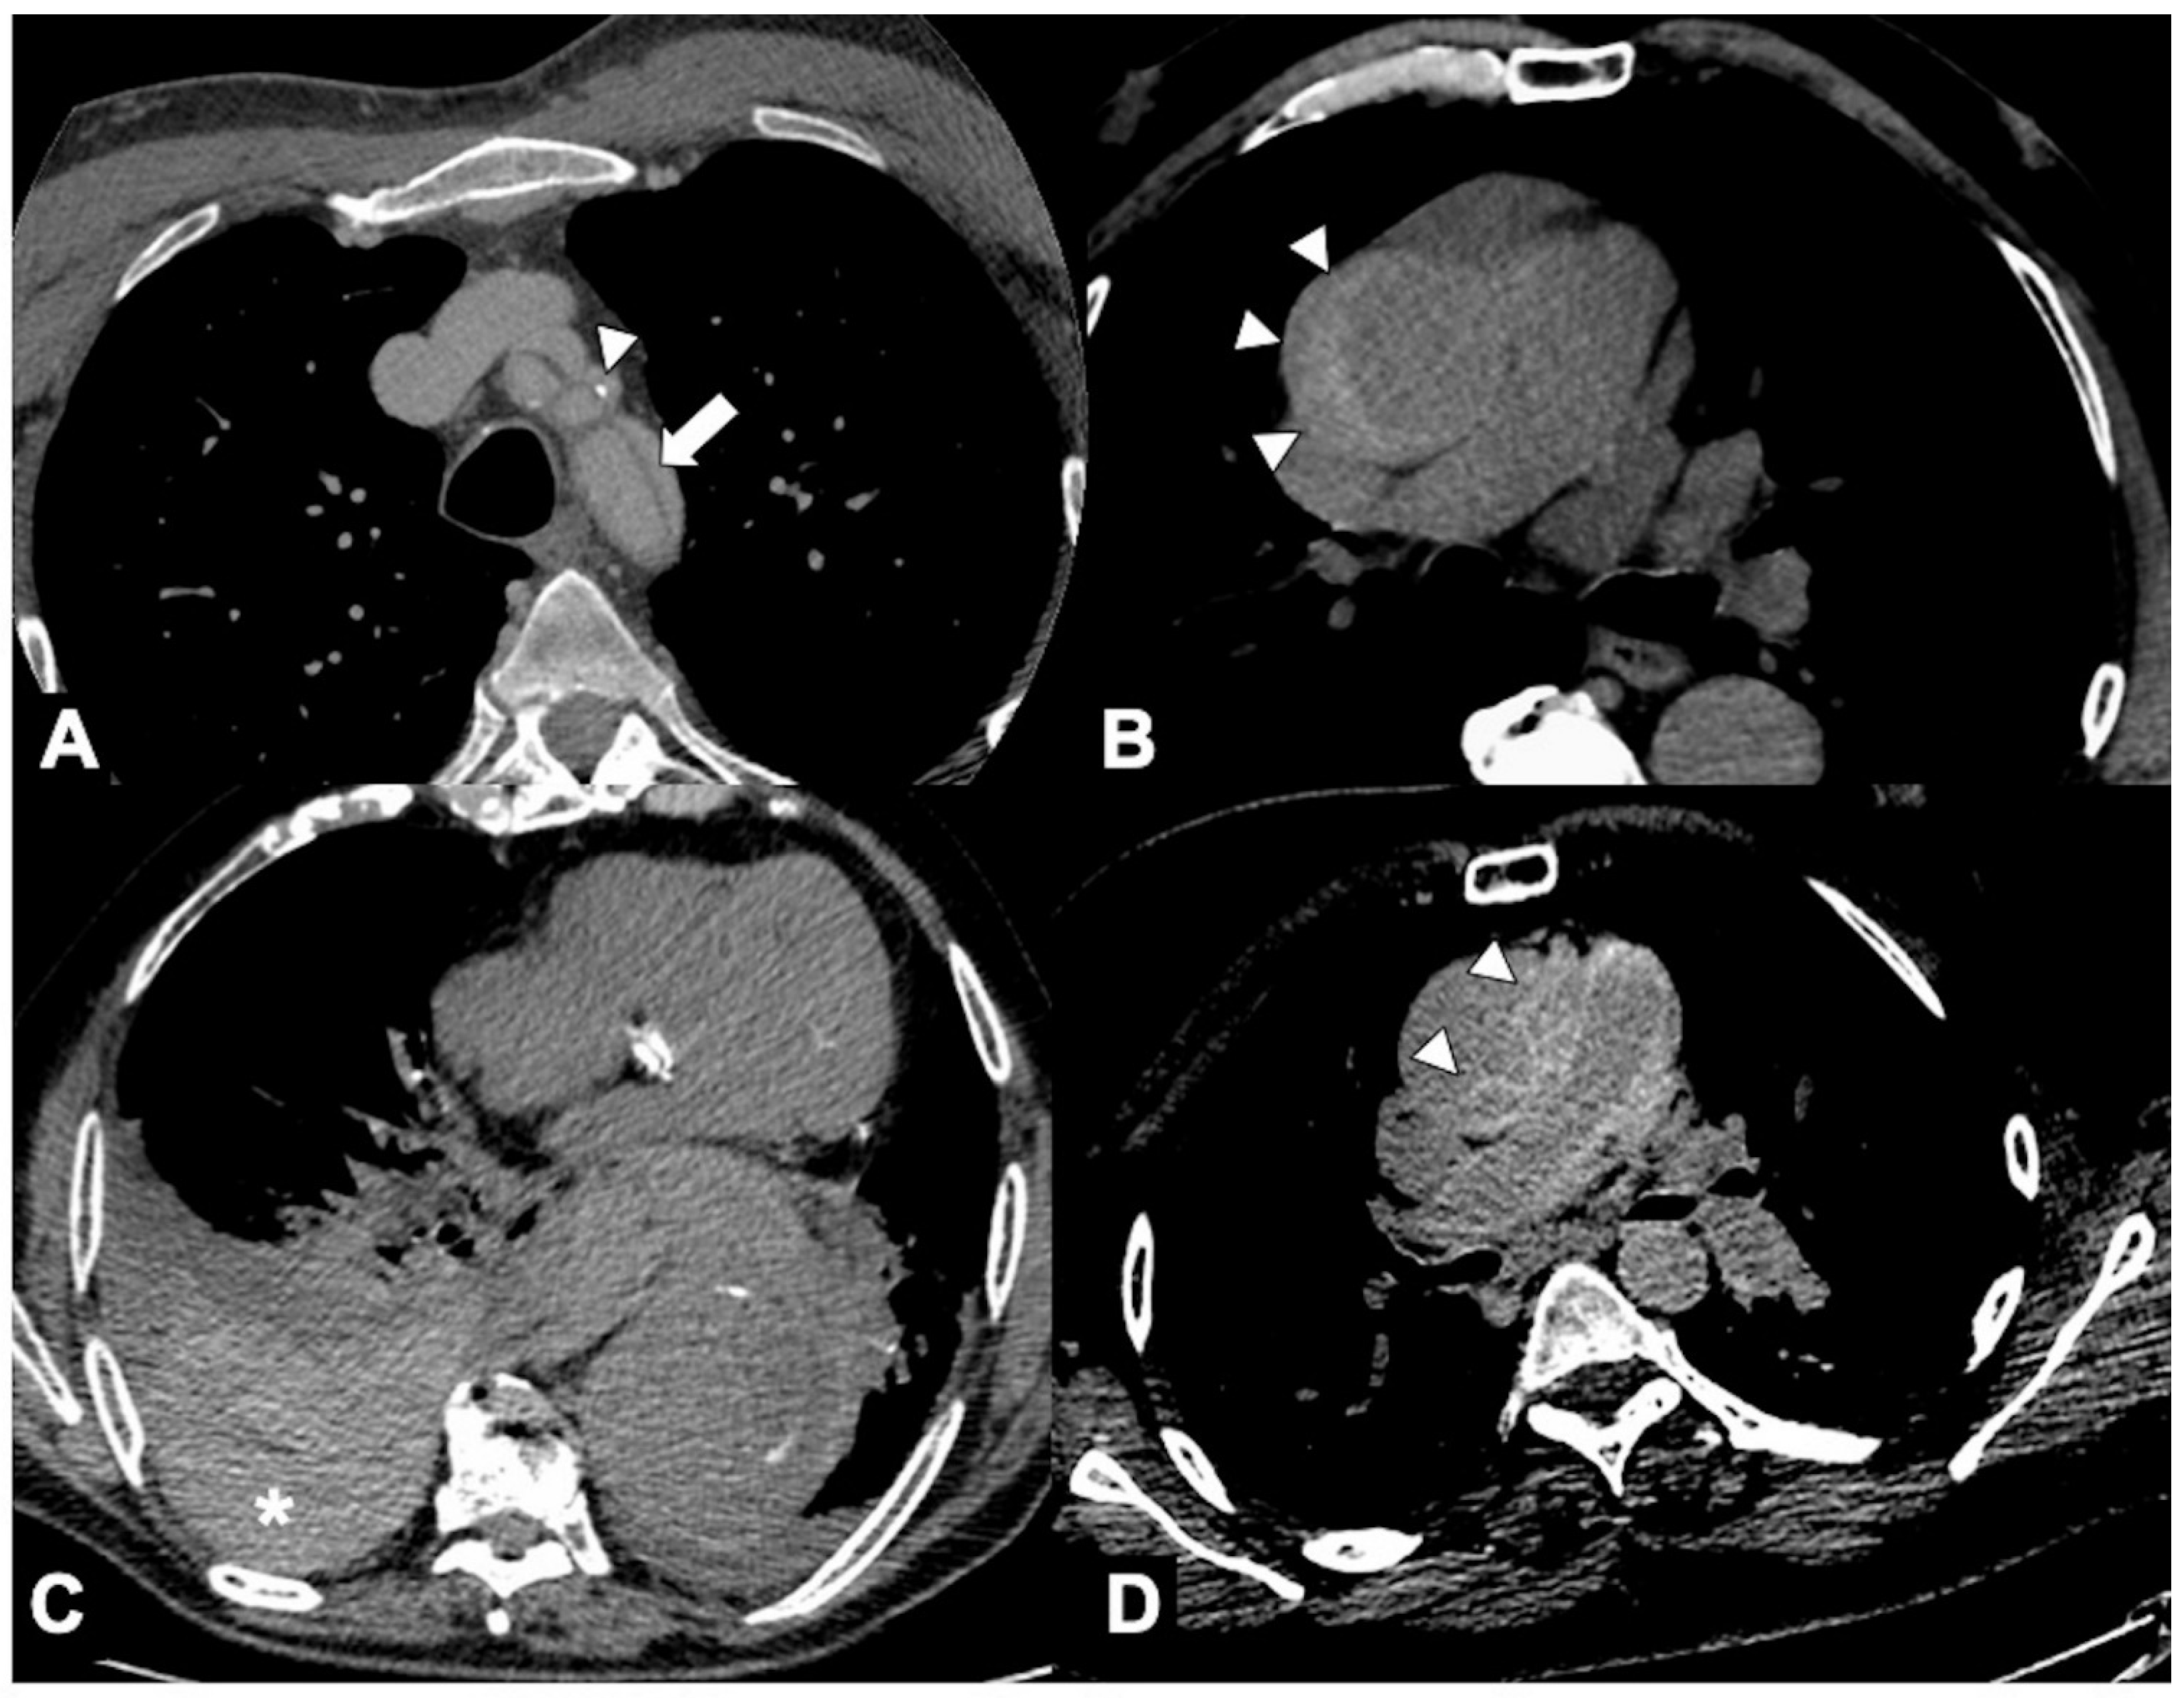

Mycotic aneurysms usually affect major arteries, classically at branch points, and have a propensity to involve the ascending aorta, which is in proximity to valves affected by endocarditis. The natural history of untreated mycotic aneurysms is dramatically fatal due to the high possibility of massive bleeding or rapidly fulminating sepsis [124]. Suggestive CTA features include new aneurysmal formation (usually saccular) with hazy and irregular contours, the presence of eccentric thrombus, rapid aneurysmal expansion, and morphological change in the shape of the aneurysm (Figure 14); synchronous aneurysms are not rare, with periadventitial enhancement and intramural or perivascular gas, oedema, soft tissue mass, or stranding of the periaortic fat [125].

Figure 14. CTA of aortitis and periaortitis by Salmonella species. A 68-year-old man with chills, high temperature, and upper back pain radiating to anterior chest. (A) Unenhanced CTA axial image shows marginal periaortic tissue (asterisk) at aortic isthmus level. (B) Axial CTA late phase image also shows a focal outpouching (curved arrow) of contrast material emanating from the isthmus. (C,D) Axial arterial and delayed-phase CTA images obtained 7 days later show that contrast outpouching was considerably larger (curved arrows), a finding referable to rapidly growing focal mycotic pseudoaneurysm, and the patient underwent endovascular aortic repair and intravenous antibiotic therapy.